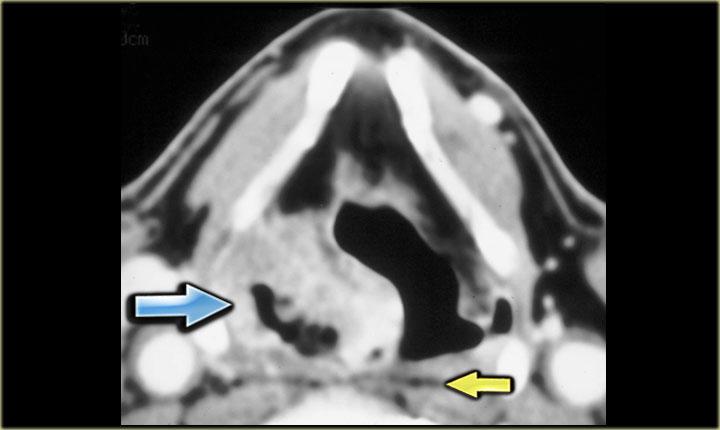

Bên trái là hình ảnh một bệnh nhân có khối phồng ở bên phải cổ.

Hãy quan sát hình ảnh và xác định tổn thương nằm trong khoang nào.

Khối phồng nằm trong giới hạn của sụn giáp.

Do đó, đây phải là bệnh lý xuất phát từ khoang tạng.

Lát cắt CT cho thấy tổn thương ở mức thanh quản trên thanh môn và sụn giáp.

Vì vậy, chúng ta đang ở vị trí quá cao so với khí quản, tuyến giáp, tuyến cận giáp và thần kinh thanh quản quặt ngược, vốn nằm trong rãnh khí quản-thực quản.

Bên trái là hình CT ở mức sụn giáp.

Có một khối không đều nằm trung tâm ở xoang lê bên phải.

Khối này nằm trong khoang tạng.

Ở vùng này, khối u thường gặp nhất là ung thư biểu mô tế bào vảy.

Chẩn đoán này đã được xác nhận qua sinh thiết.

Lưu ý khoang sau hầu (mũi tên vàng).

Đây là khoang ảo chỉ chứa một ít mô mỡ.